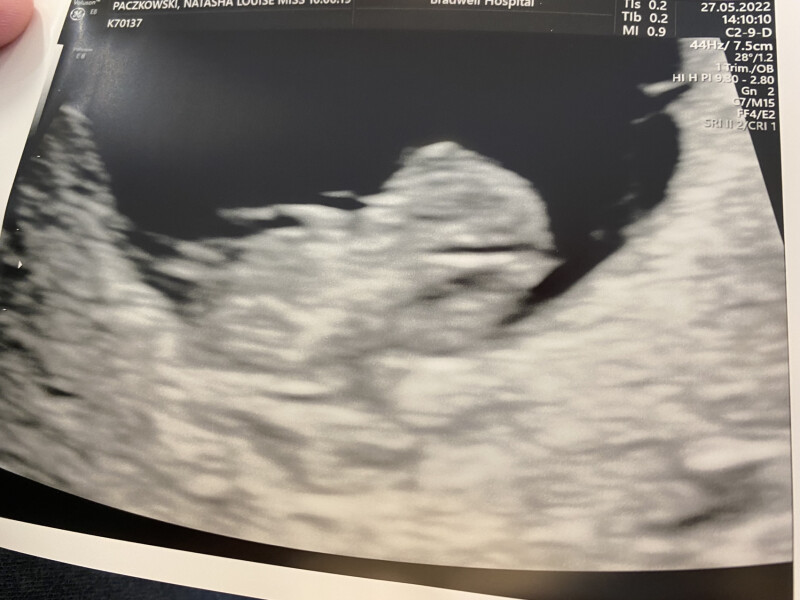

tasha4eva10 · 27/05/2022 20:25

Had our scan today and baby is measuring exactly as he/she should be, sticking their arm up in the air and stretching the legs out which I thought was quite funny for 9 weeks!

@lovesT @F03t @tasha4eva10 lovely scans!!